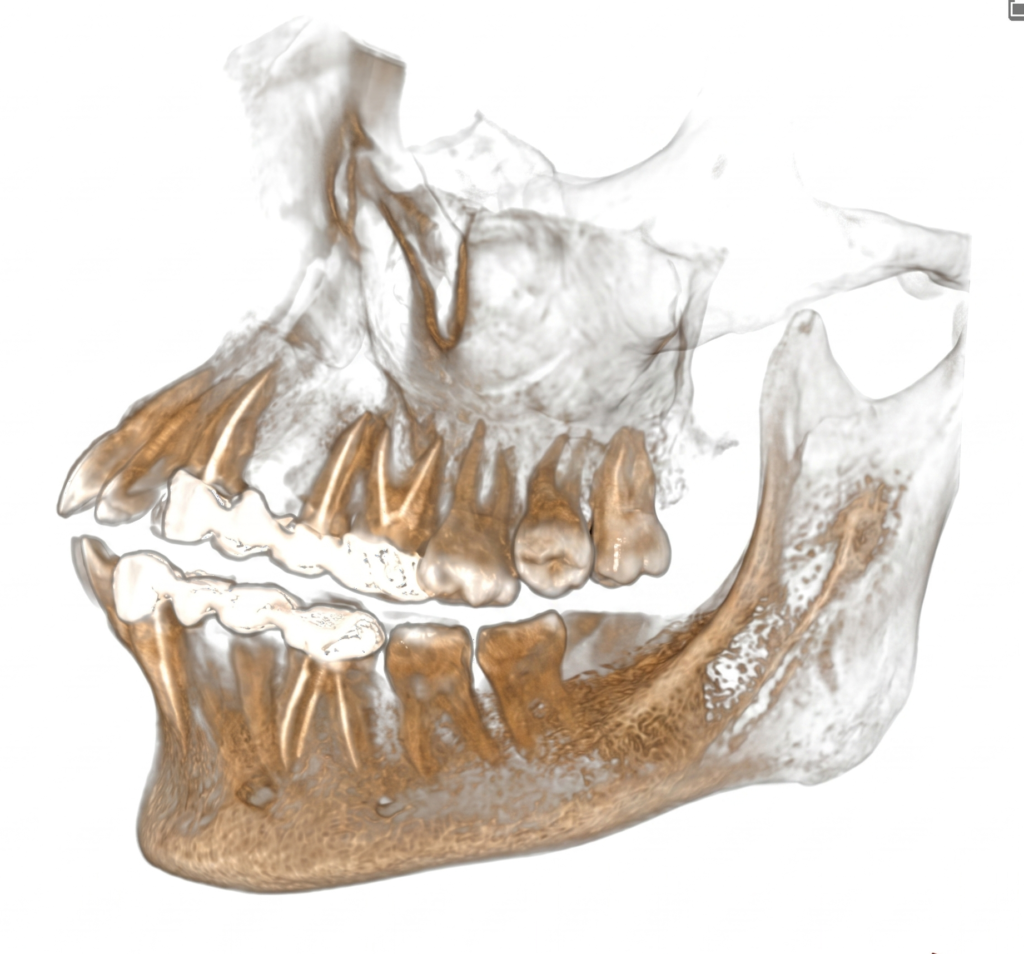

He is certified in Cone Beam Computed Tomography (CBCT) and has extensive experience in advanced radiological diagnosis. Dr. Singh is associated with several reputed centers across India as a consultant radiologist for CBCT reporting. His expertise includes implant planning, impacted teeth localization, oral and maxillofacial pathology interpretation, TMJ assessment, maxillary sinus evaluation, and airway analysis.

Single tooth (If impacted or partially impacted) 1500/-

Quadrant CBCT 1500/-